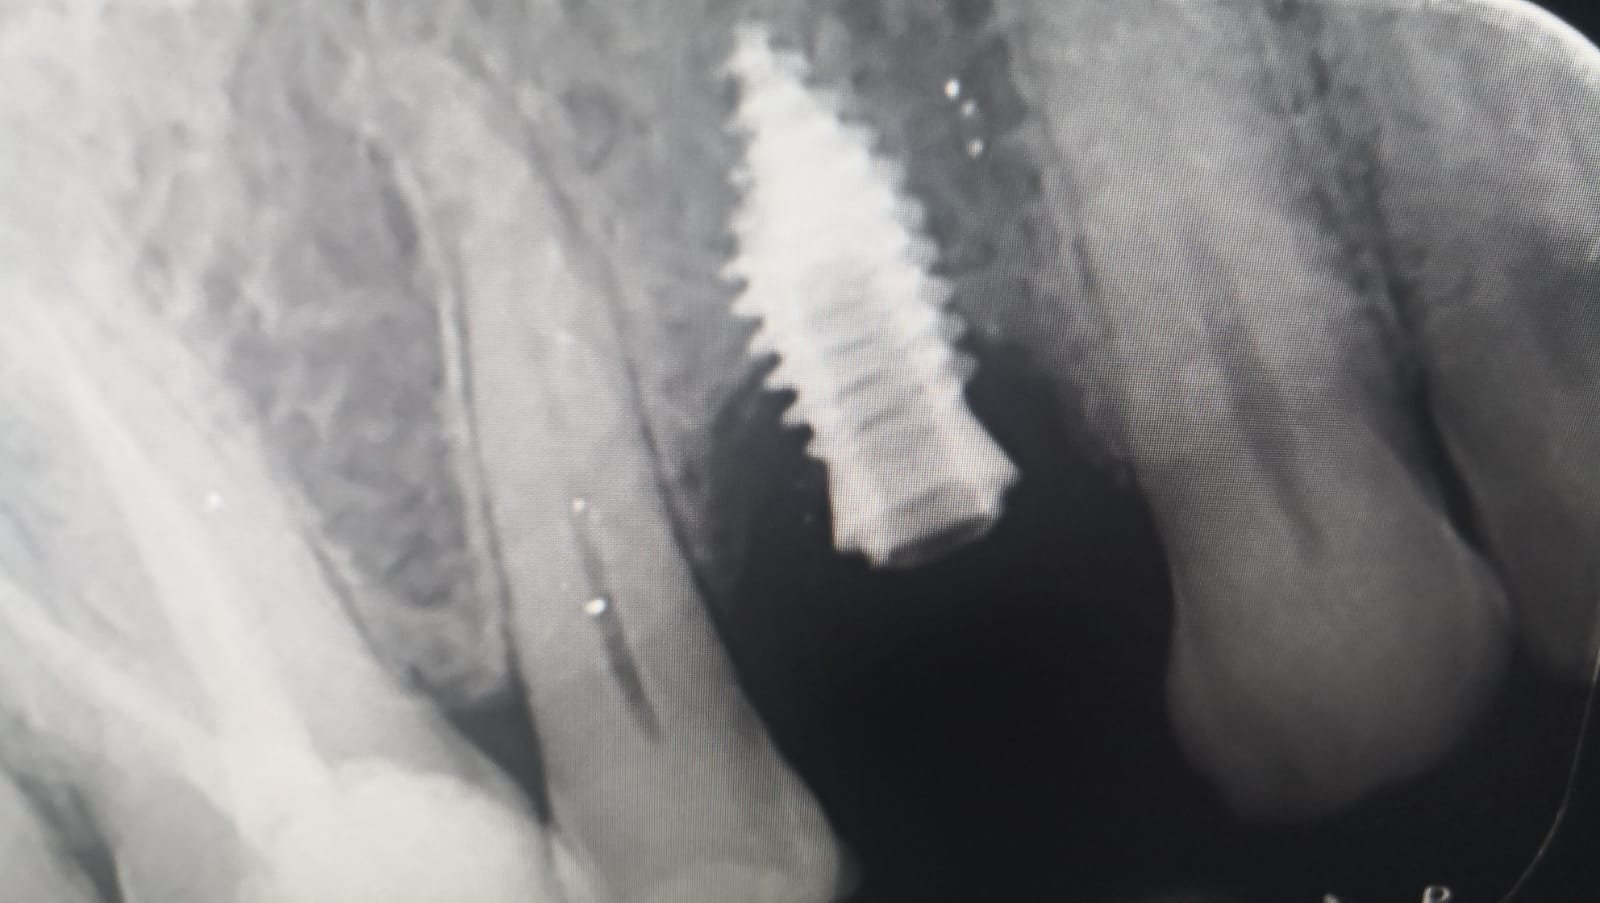

Paciente acude a consulta para rehabilitación,creo que todos son de Ziacom,el que no se identificar es el implante del segundo cuadrante,el más posterior que lleva injerto,si podéis ayudarme a identificarlo,la [...]